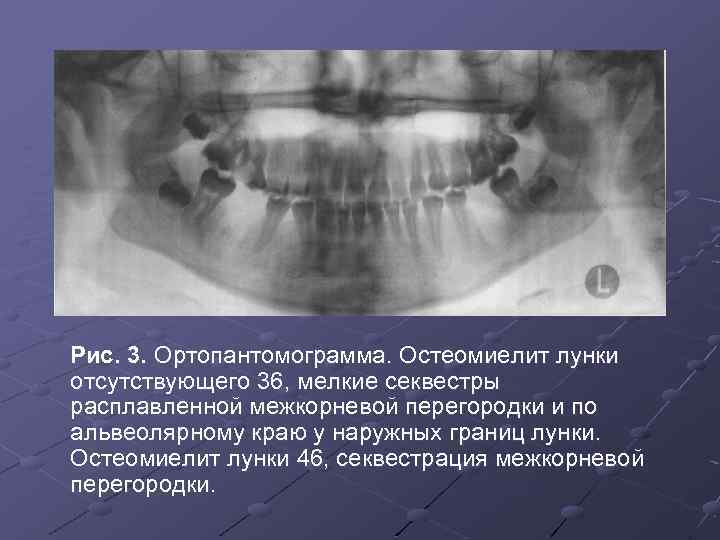

Анатомия: Межкорневая костная перегородка

Раздел: Галерея впечатлений